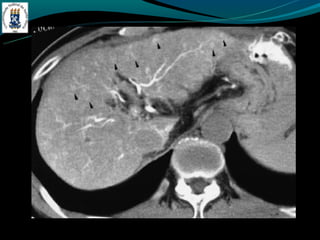

GÁS NO SISTEMA PORTA

-Mais frequentemente associado:

-Isquemia intestinal nos adultos

-Enterocolite necrosante nos RN

-Outras causas: colonoscopia recente, sonda de gastrostomia, DII,

diveticulite, abscesso abdominal…

GÁS NO SISTEMAPORTA -Mais frequentemente associado: -Isquemia intestinal nos adultos -Enterocolite necrosante nos RN -Outras causas: colonoscopia recente, sonda de gastrostomia, DII, diveticulite, abscesso abdominal…